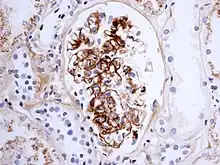

As observed under methods of histopathology, acute necrotizing vasculitis within the affected tissues is observed concomitant to neutrophilic infiltration, along with notable eosinophilic deposition (fibrinoid necrosis). Often, immunofluorescence microscopy can be used to visualize the immune complexes.[10] Skin response to hypersensitivity of this type is referred to as an Arthus reaction and is characterized by local erythema and some induration. Platelet aggregation, especially in microvasculature, can cause localized clot formation, leading to blotchy hemorrhages. This typifies the response to injection of foreign antigen sufficient to lead to the condition of serum sickness.[11]